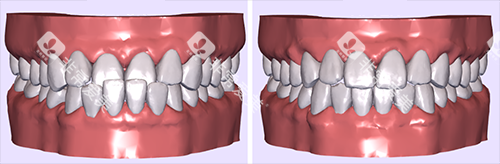

晓庄口腔门诊位于会前路立体城凌江庭第八九十十一栋202室,其牙齿矫正项目颇受关注。

诊所引进了多种正畸系统,如金属托槽矫正、无托槽隐形矫正和陶瓷半隐形矫正等,还推行智能化正畸技术,提高了矫治效率,缩短了佩戴牙套的周期。